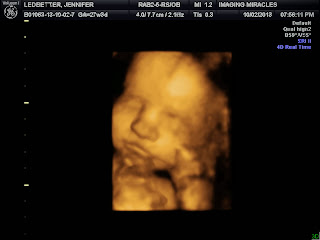

Okay, I've really been slacking. BUT we are in our 3rd trimester now and I have 3d pictures!! :) The grandparents offered to treat us to a peak at our BEAUTIFUL daughter! We went to a new place and she did an amazing job at getting Kaitlyn positioned to get perfect pictures! Check them out!

Right now Kaitlyn should be about 2lbs and 14.5 inches long. As we saw on the ultrasound, she is sucking, opening her eyes, and likes to curl up like a pretzel and play peek-a-boo! :)